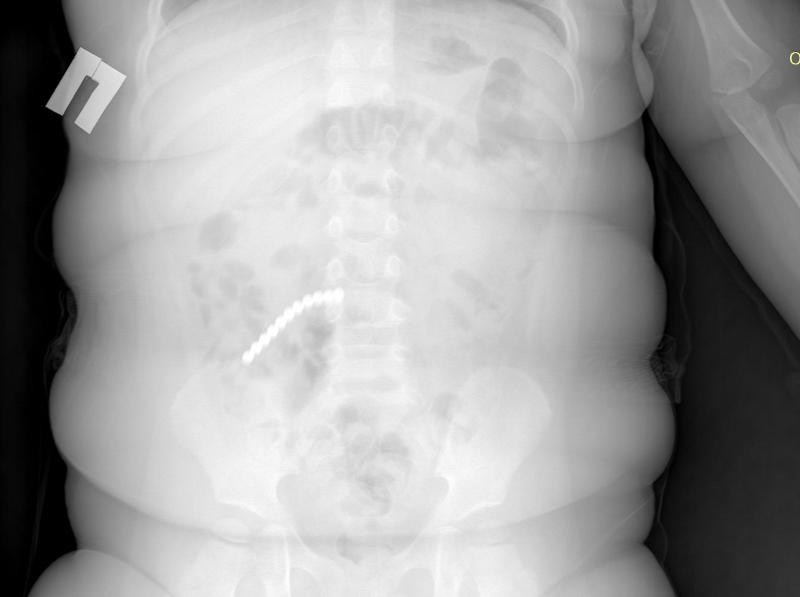

Малыш проглотил 20 магнитных шариков, что привело к дыре в кишечнике, экстренному хирургическому вмешательству и удалению части тонкой кишки. Медики настаивают: подобные игрушки не должны находиться в руках детей, так как несут прямую угрозу их жизни. Так в начале февраля ребенок поступил в приемно-диагностическое отделение ДРКБ с рвотой и ухудшением состояния. Рентгенография сразу выявила причину — множество инородных тел в пищеварительном тракте. Снимок показал 20 магнитных шариков от неокуба.

— Нам удалось удалить 9 штук магнитов эндоскопически (ФГДС). Однако остальные мигрировали по кишечнику, вызвав перфорацию. Петли тонкой, сигмовидной и слепой кишки слиплись между собой из-за магнитного притяжения, — пояснил врач-хирург-эндоскопист ДРКБ Булат Шагдаров.